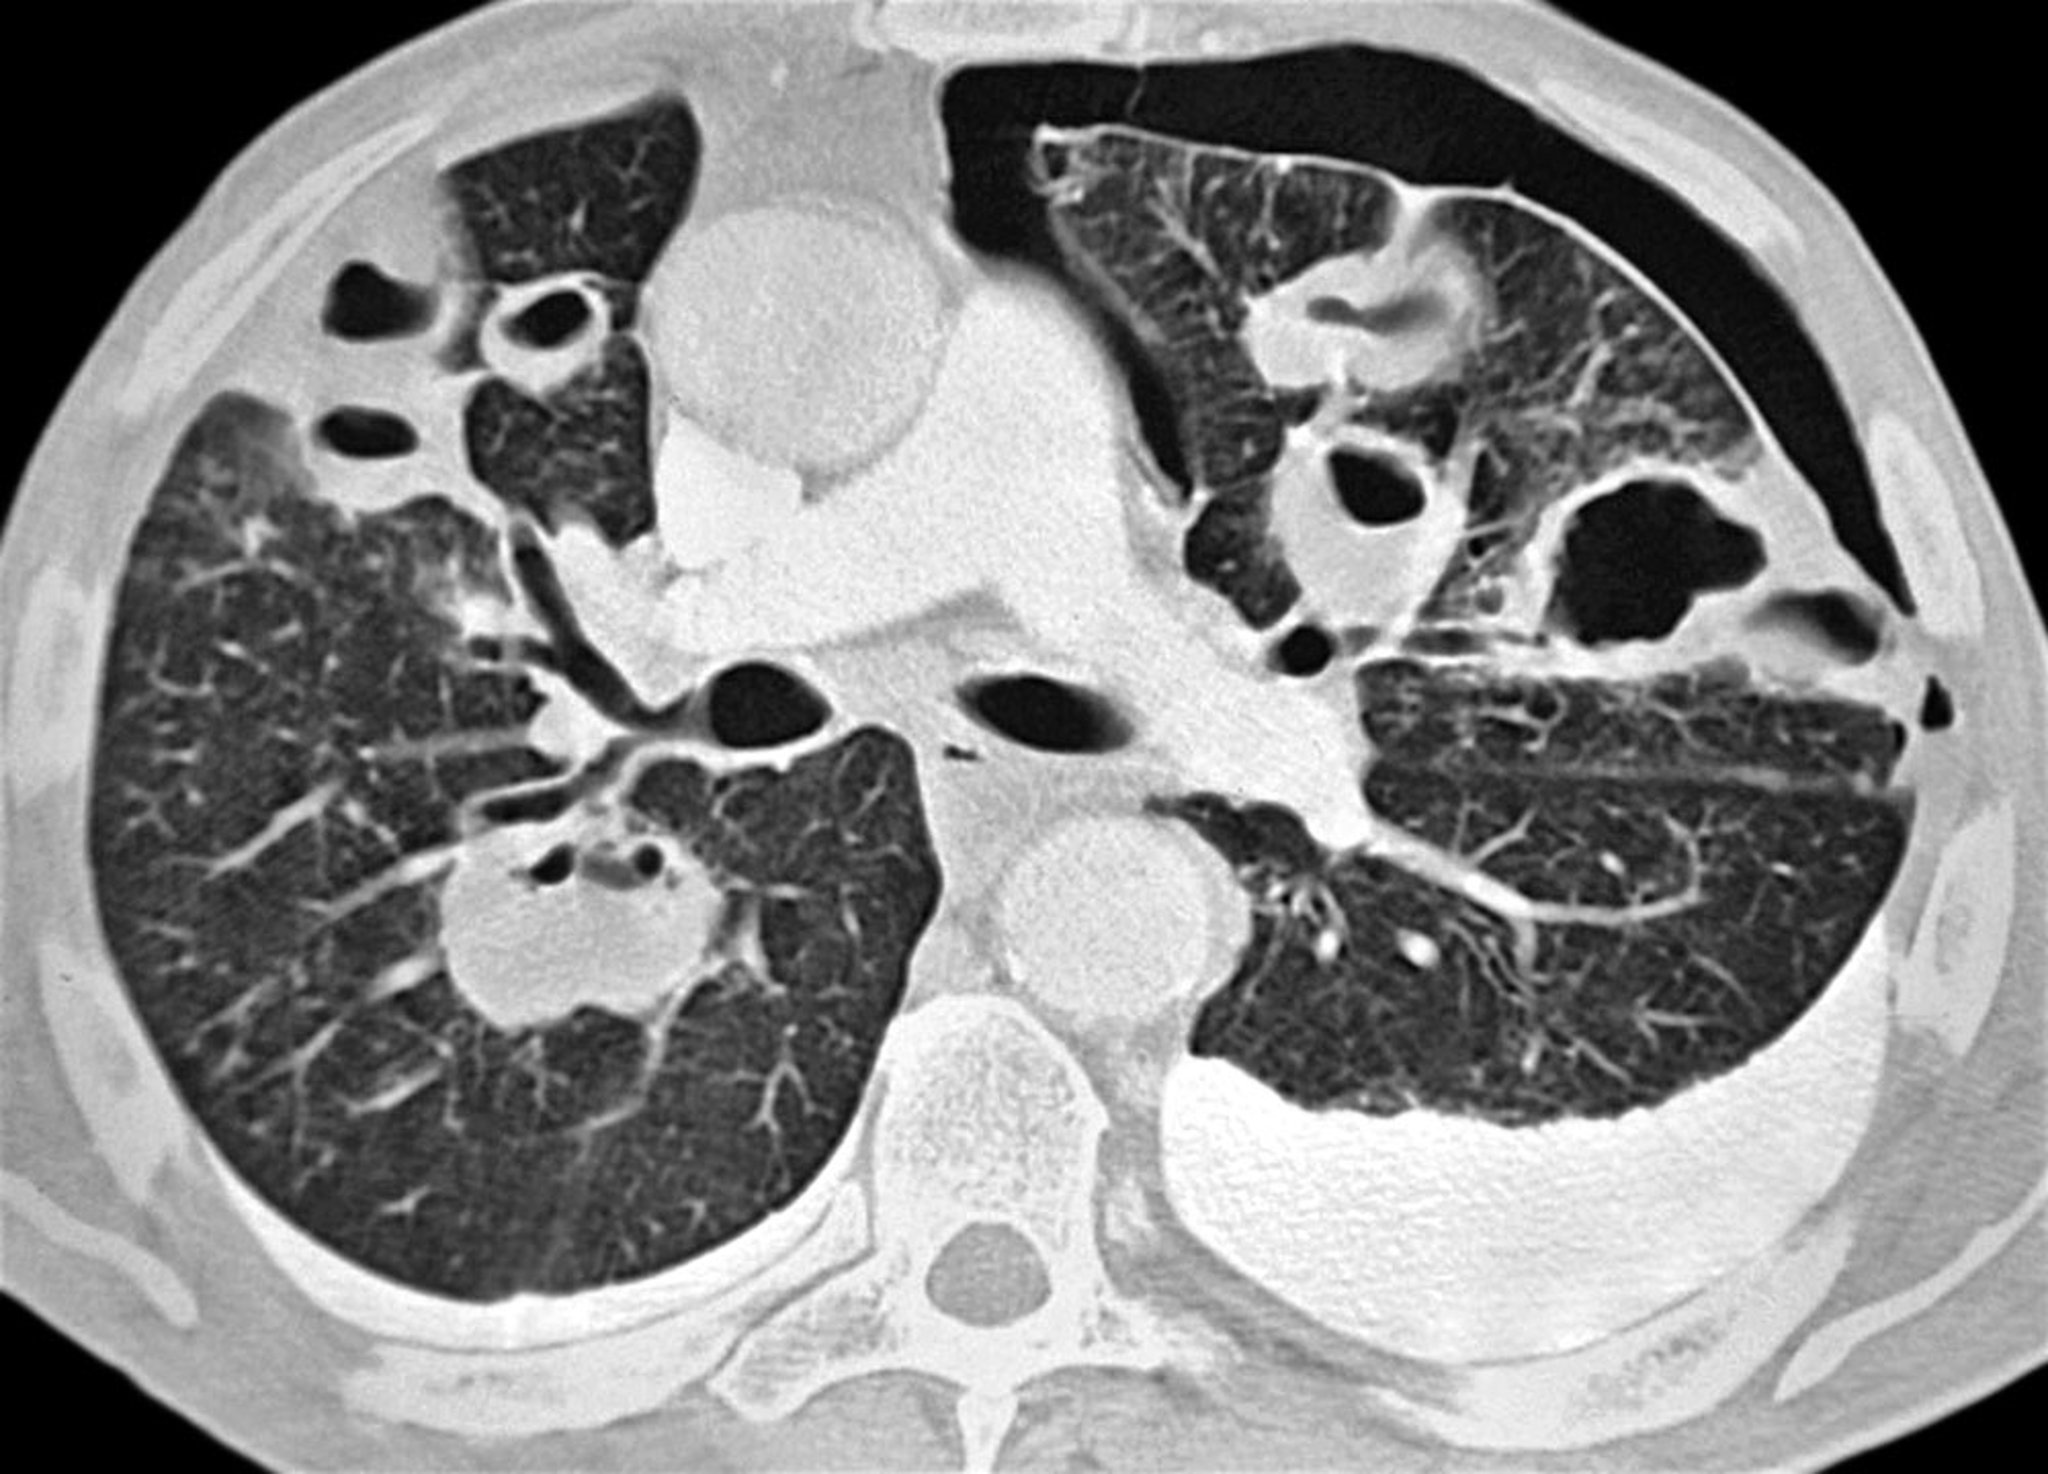

该轴位CT显示细菌性肺炎患者存在左侧气胸。可见多发脓肿及双侧胸腔积液(左侧更明显)。